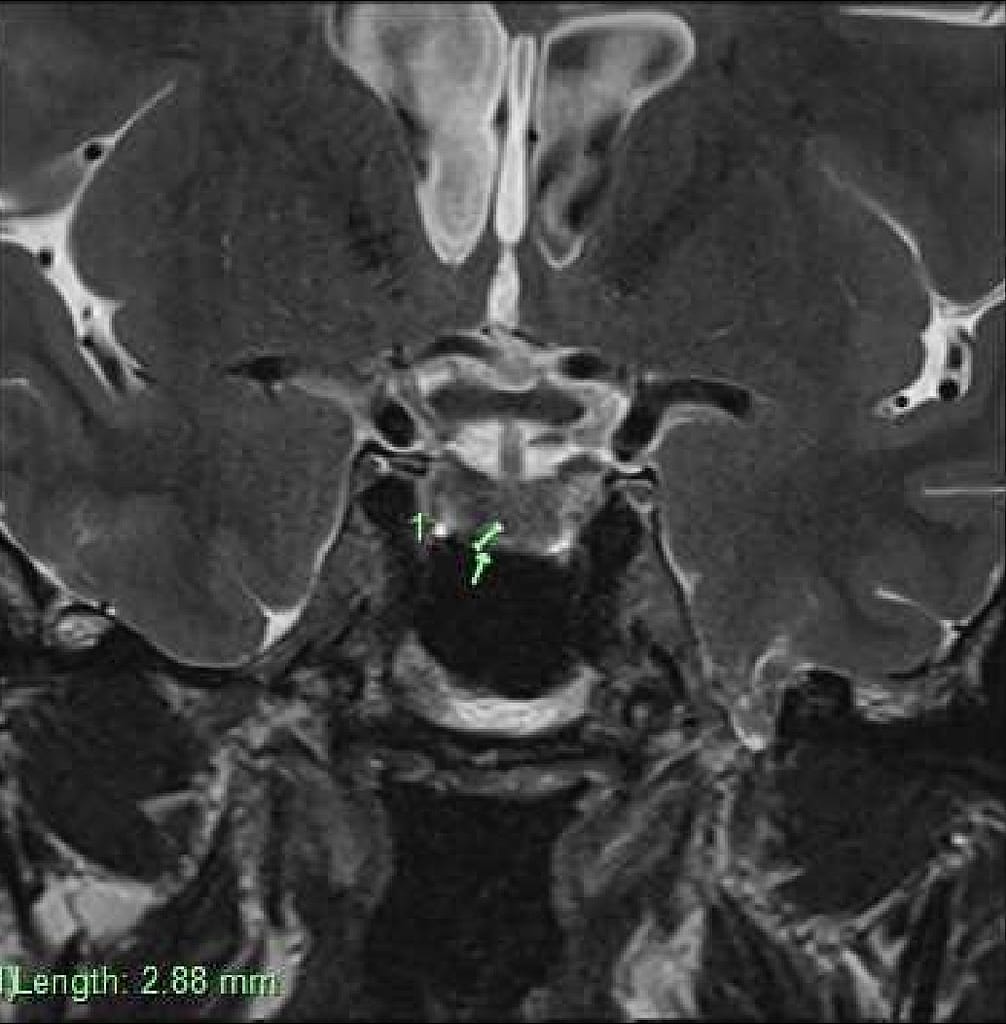

I opted for being safe than sorry. So, I visited the local optometrist to have my eyes tested. They strongly advised I go back to see Dr Tollesson. He then ordered the MRI. While there was no explanation for what caused the episode of vision loss, known as hemianopia, the incidental finding of the pituitary tumor has now alerted Dr Tollesson to what we need to focus on next. I recall him saying that due to the location, if it were bigger, it would cause pressure on the optic nerve as it grows, and explain loss of vision. Regardless, it’s not the cause based on the imaging he was looking at. It’s too small and currently classed a micro adenoma, should it grow in size, it will be called a macro adenoma.

Pituitary tumor imaging

2.58mm in length